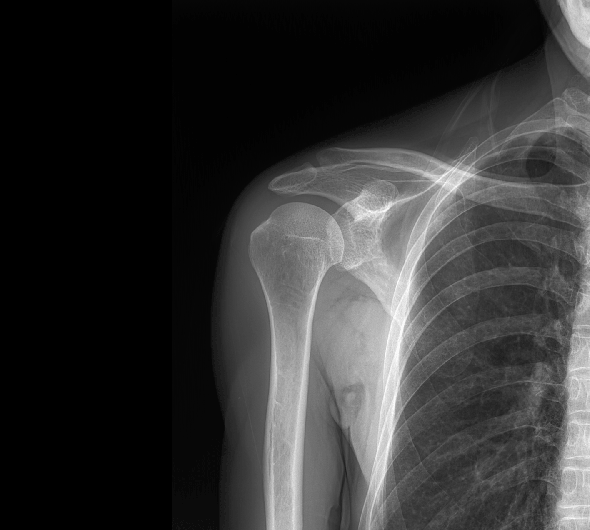

臨床圖像